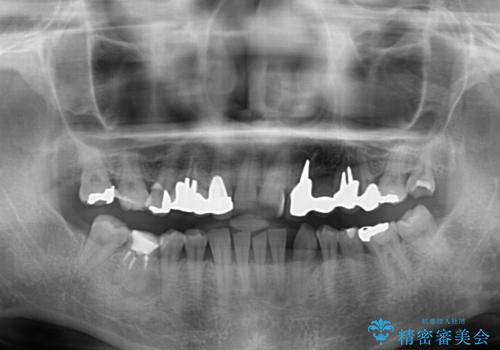

- 割れていると言われて放置してしまった歯や、前歯のデコボコなどが気になるとのことで来院された患者様です。

左上の歯は割れてしまっており、抜歯のうえインプラント治療が必要であり、他にも抜歯の必要な歯がある状態でした。

上顎はほぼ全ての歯をセラミッククラウンにて補綴治療を行う必要があるため、気になるデコボコや深い咬み合わせを改善するために下顎と上顎の臼歯部の矯正治療を行うこととしました。

並行して左下にはインプラントを埋入し、矯正治療を終えると同時に補綴治療を行うこととしました。

過蓋咬合(下顎前歯が隠れてしまうほどの深い咬み合わせ)のため、スムーズに歯が動かず矯正治療に時間がかかりましたが、無事に仕上げることができました。